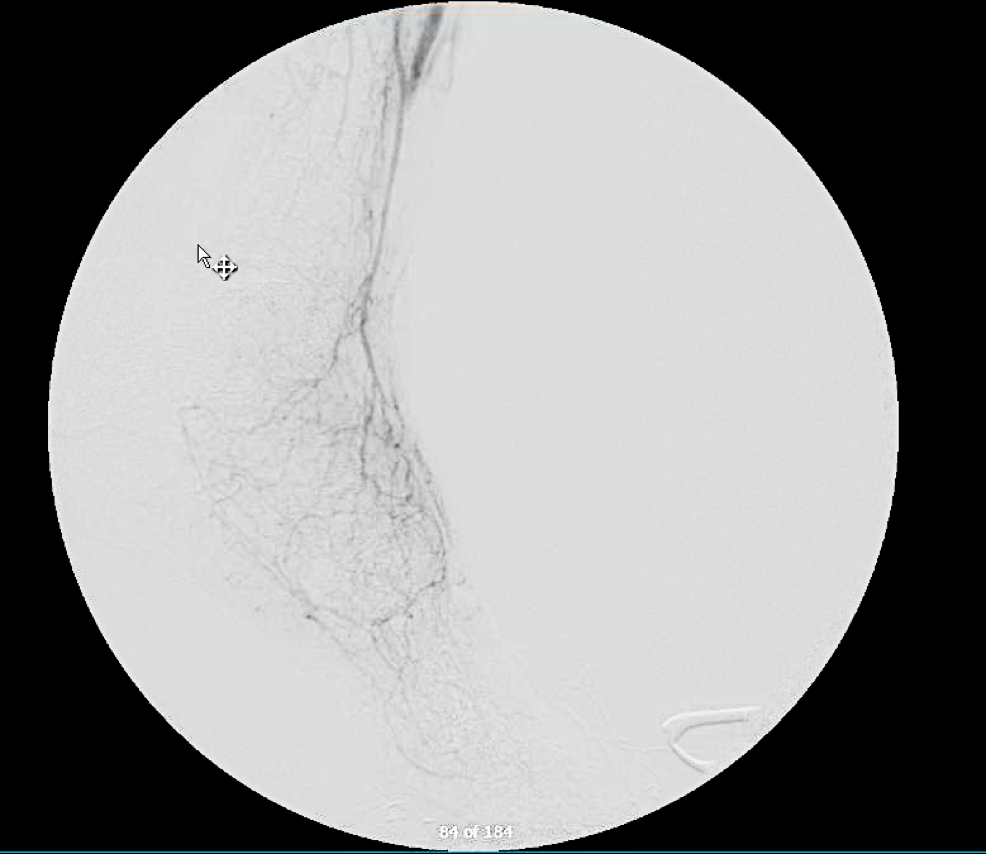

On examination, she was a large woman with no femoral pulses, but signals could be obtained in her popliteal and tibial arteries. Her PVR’s showed inflow disease and poor flow at the feet.

At followup several months after the procedure, the patient was walking well without claudicating and was ready to return to work. PVRs showed excellent flows down to the toes.